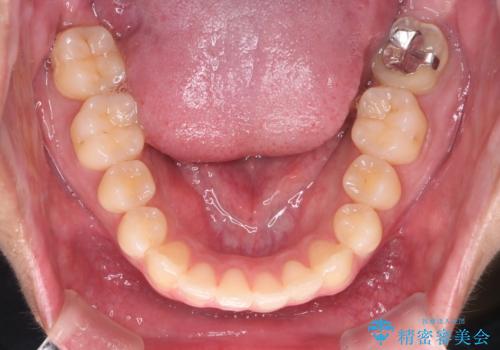

- 上の八重歯と下の歯のがたつきを主訴に来院されました。

矯正検査の結果、抜歯はせずに

臼歯を遠心移動させ、歯列をワイヤーで整えることでスペースを確保し、IPR(歯と歯の間を削る処置)を加えて歯並びを綺麗にする治療計画を立てました。